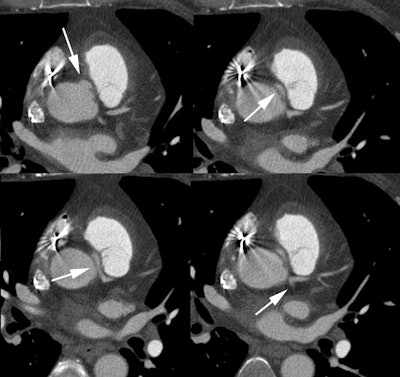

Anomalous RCA origin from the left coronary sinus: The patient below underwent coronary CT angiography to assess for coronary artery disease. The patient was found to have an anomalous RCA arising from the left sinus of valsalva. The vessel can be seen to course between the pulmonary trunk and aorta (black arrows). |